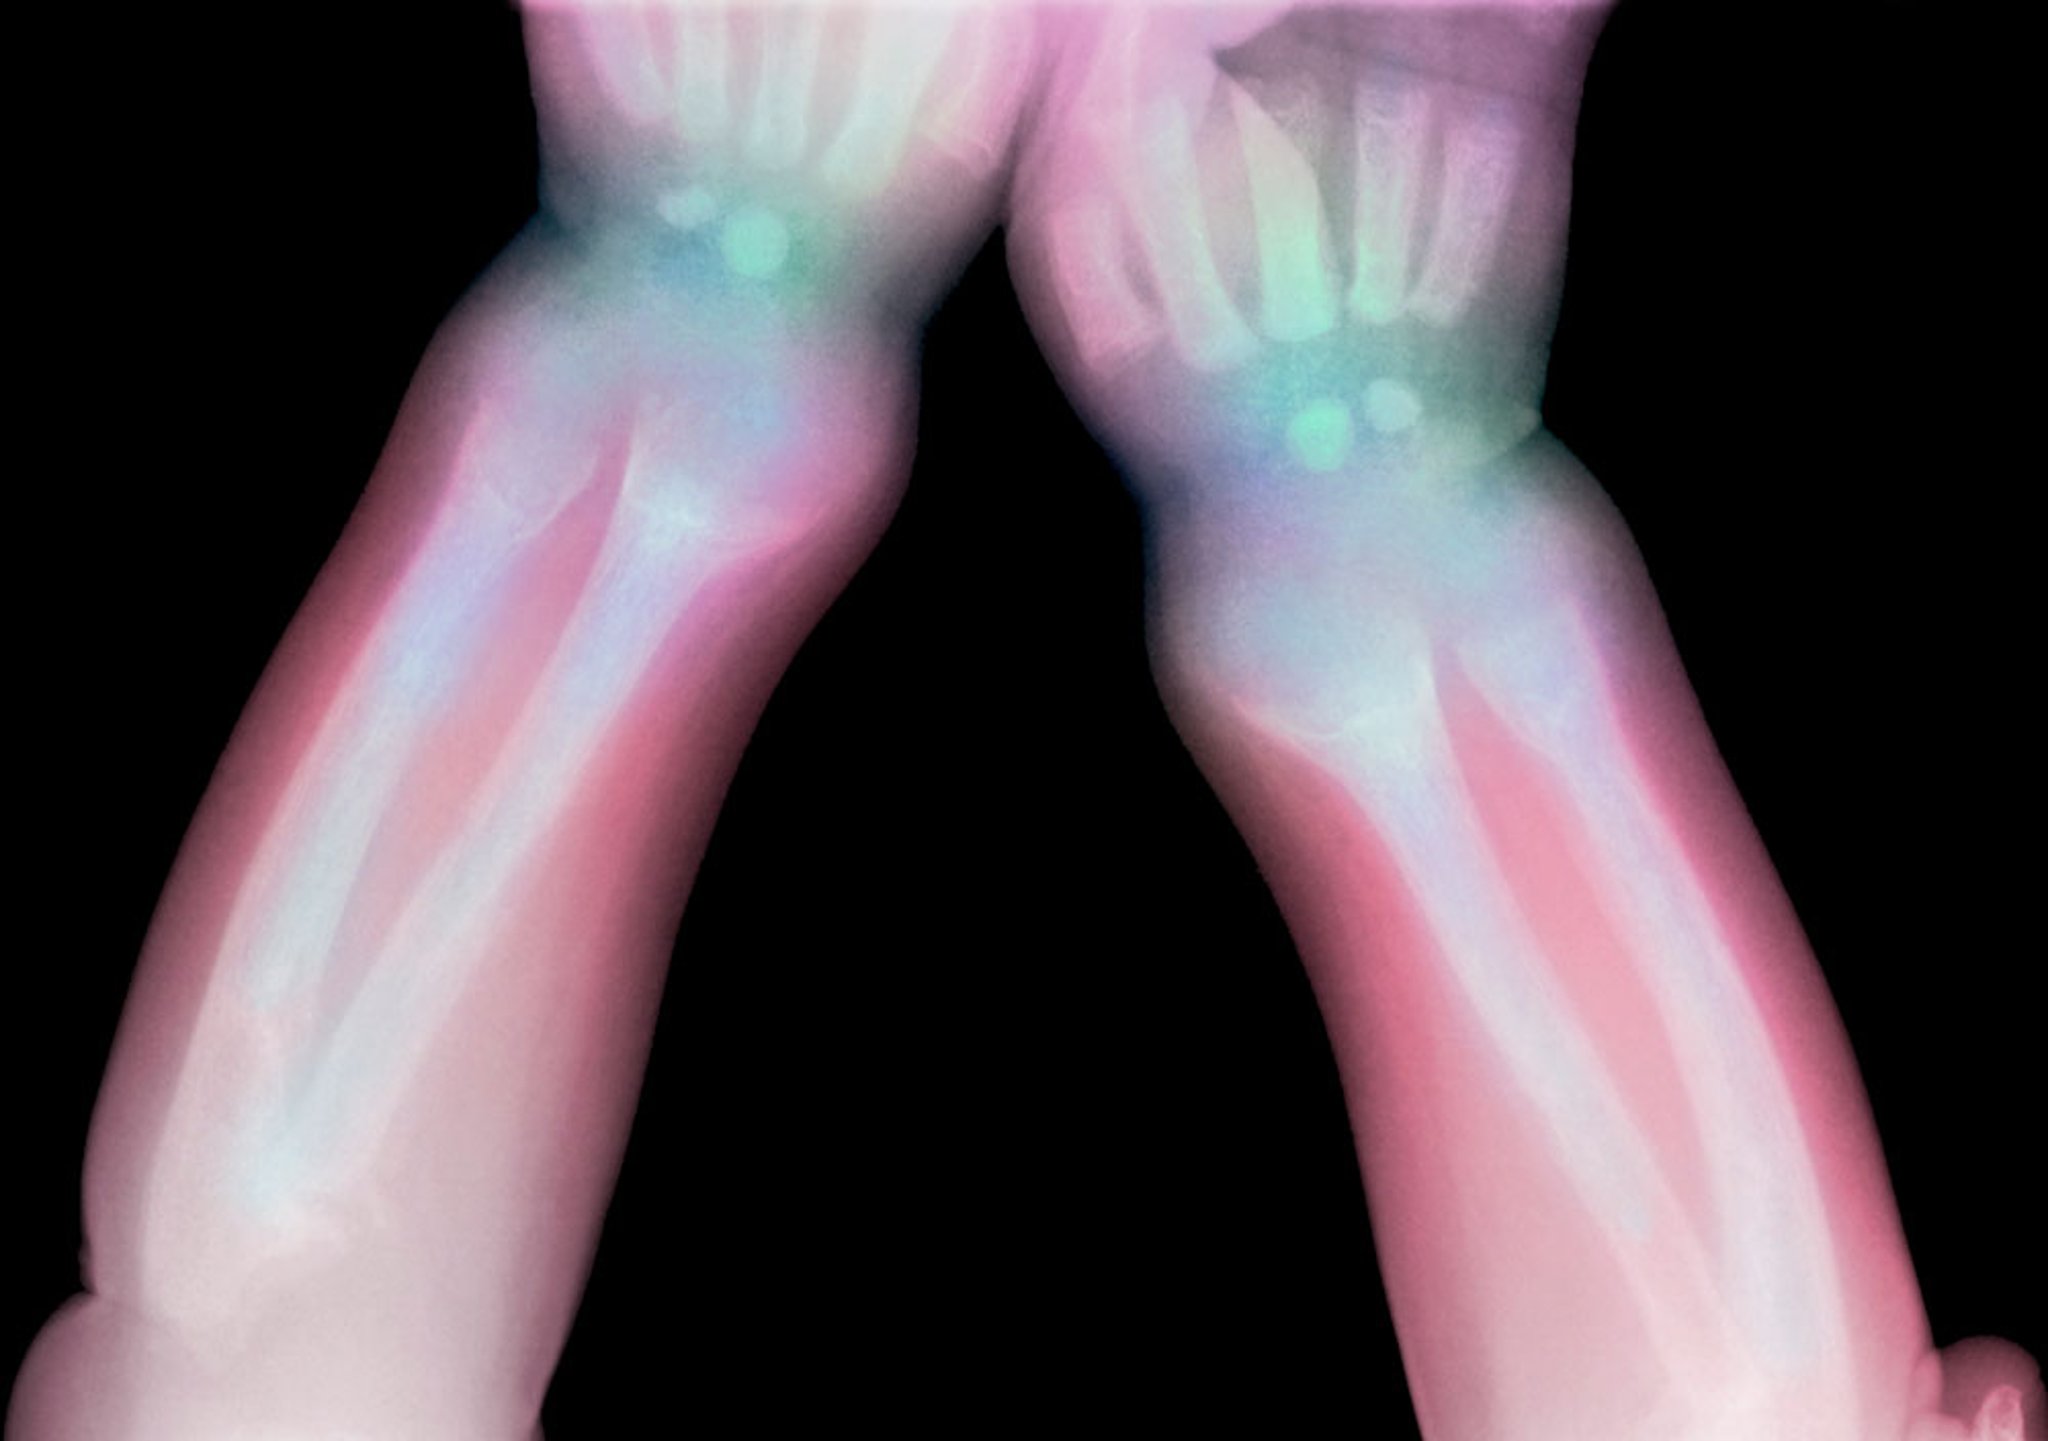

This radiograph shows lucency of the distal radius and ulna in a child with rickets.